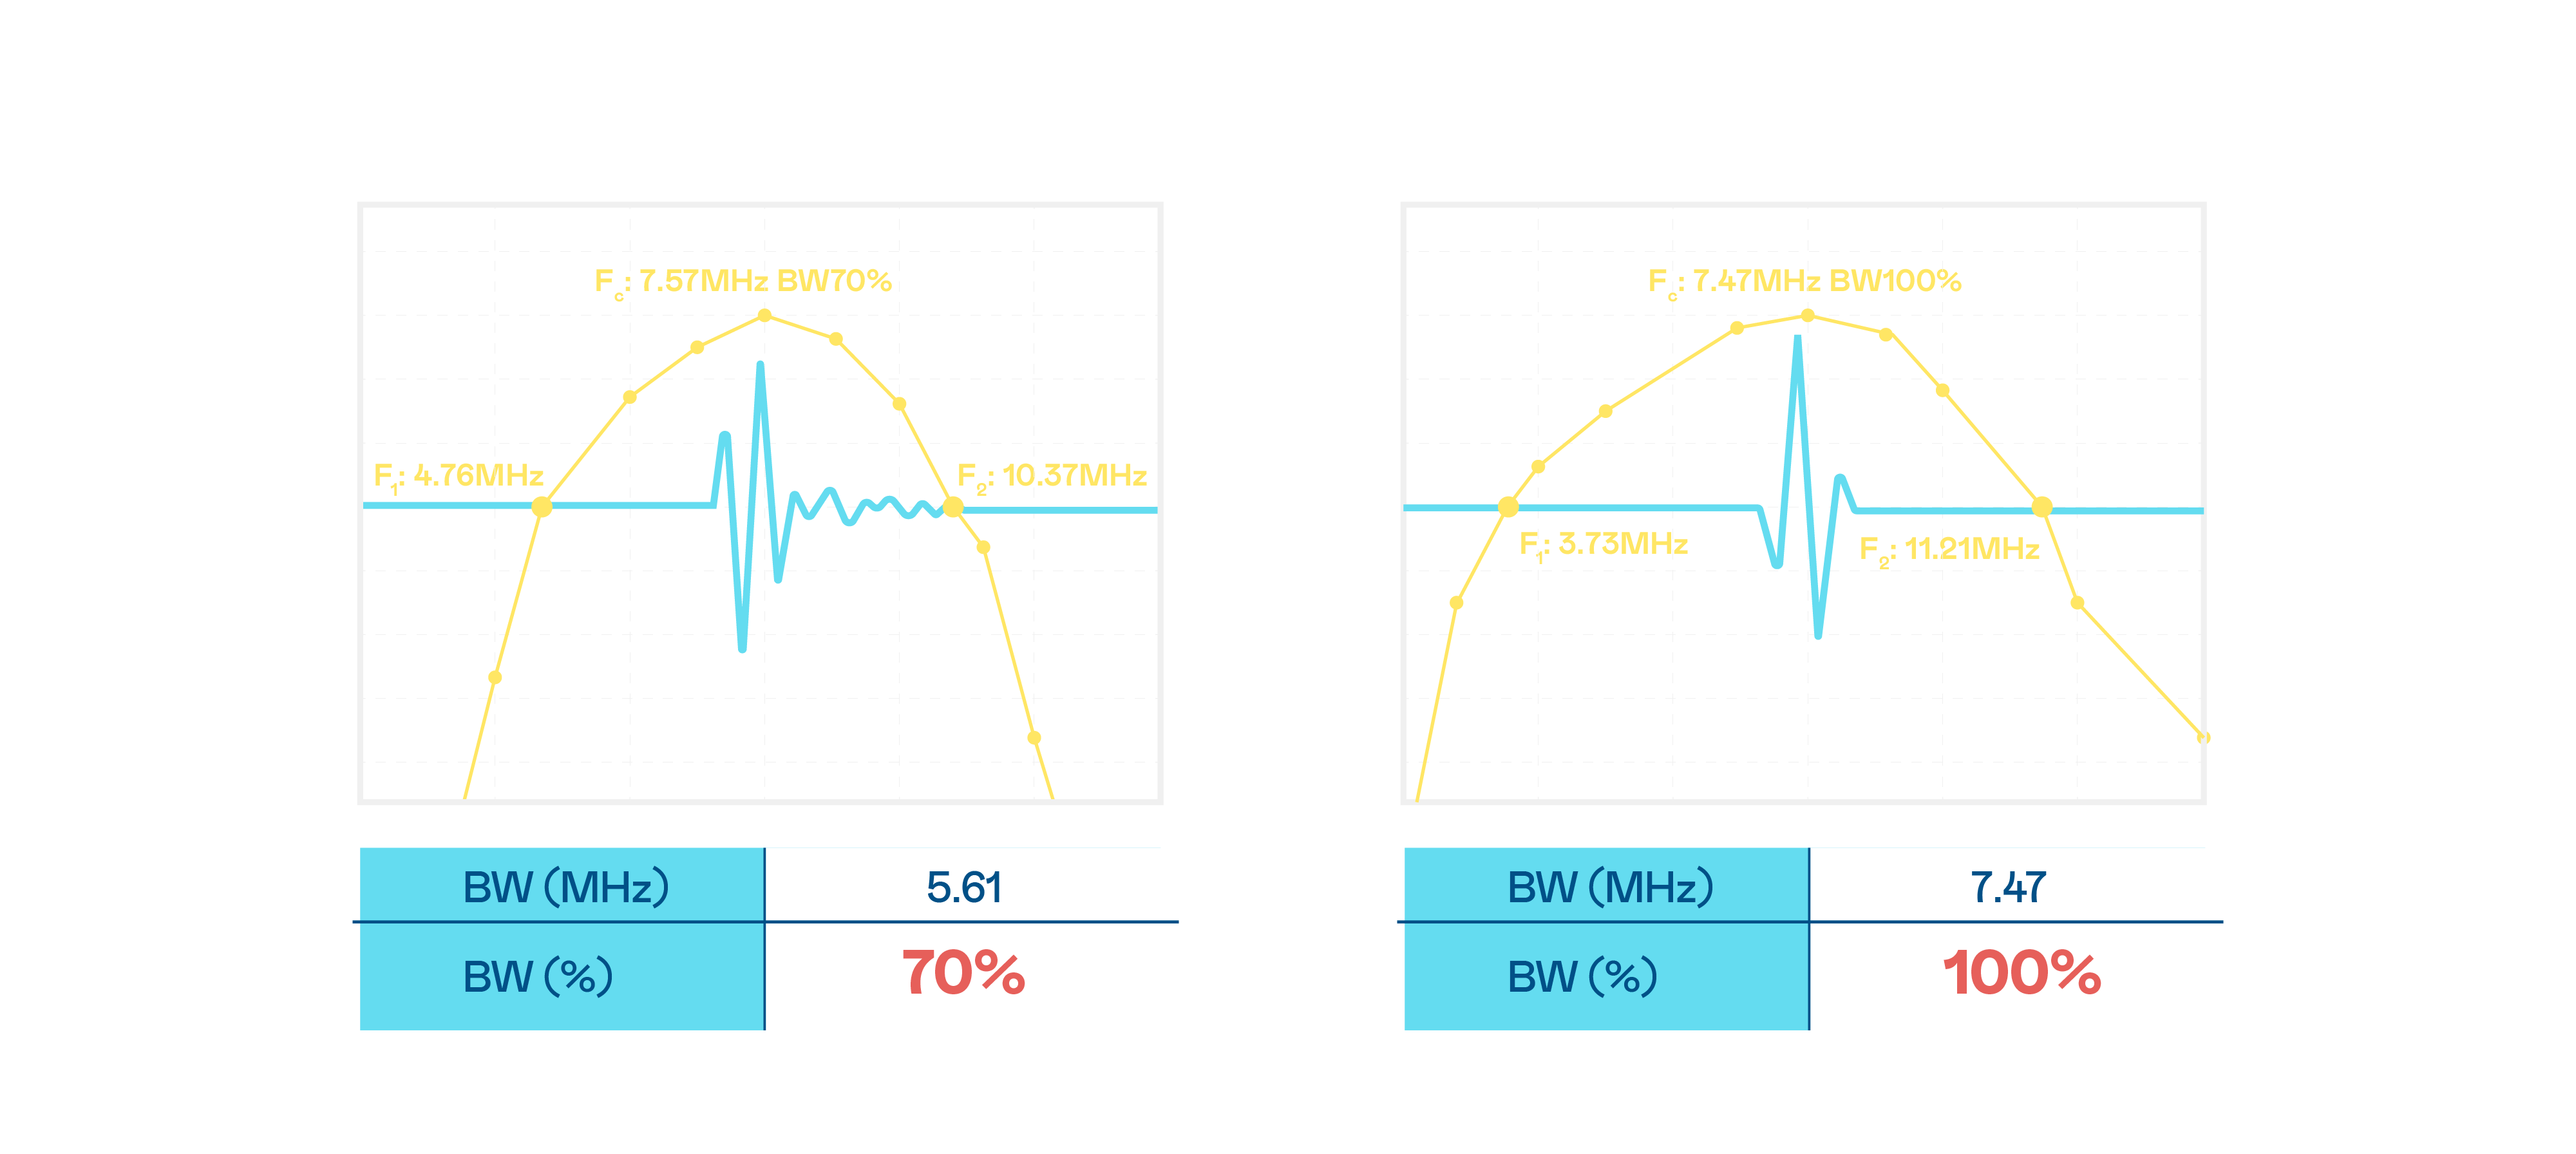

CMUT жҠҖжңҜжҳҜдёҖз§Қз”Ёз”өе®№ејҸеҫ®жңәз”өе…ғ件жқҘдә§з”ҹи¶…йҹіжіўи®ҜеҸ·зҡ„жҠҖжңҜгҖӮдёҺдј з»ҹ PZT еҺӢз”өејҸжҠҖжңҜзӣёжҜ”пјҢCMUT йў‘е®ҪеўһеҠ 30%пјҢжӣҙе®Ҫйў‘зҡ„и¶…йҹіжіўи®ҜеҸ·и®©еҪұеғҸи§ЈжһҗеәҰеӨ§е№…жҸҗеҚҮпјҢжҳҜе®һзҺ°й«ҳеҪұеғҸе“ҒиҙЁеҢ»з–—и¶…йҹіжіўжү«жҸҸгҖҒдҝғиҝӣзІҫеҮҶеҢ»з–—еҸ‘еұ•зҡ„е…ій”®жҠҖжңҜгҖӮ

и¶…йҹіжіўеҪұеғҸзҡ„и§ЈжһҗеәҰй«ҳдҪҺпјҢйҰ–е…ҲеҸ–еҶідәҺжҺўеӨҙиғҪеҸ‘еҮәзҡ„и®ҜеҸ·йў‘е®ҪгҖӮAGзҷҫ家д№җ CMUT еҸҜжҸҗдҫӣй«ҳжё…жҷ°зҡ„и¶…йҹіжіўи®ҜеҸ·пјҢжҸҗдҫӣй«ҳйў‘е®ҪгҖҒй«ҳзҒөж•ҸеәҰгҖҒеҪұеғҸзә№зҗҶз»ҶиҠӮжӣҙй«ҳзҡ„и¶…йҹіжіўеҪұеғҸпјҢеҚҸеҠ©еҢ»жҠӨдәәе‘ҳзј©зҹӯеҪұеғҸеҲӨиҜ»ж—¶й—ҙеҸҠеҲ©з”ЁзІҫеҮҶзҡ„еҢ»з–—еҪұеғҸиҝӣиЎҢиҜҠж–ӯгҖӮ